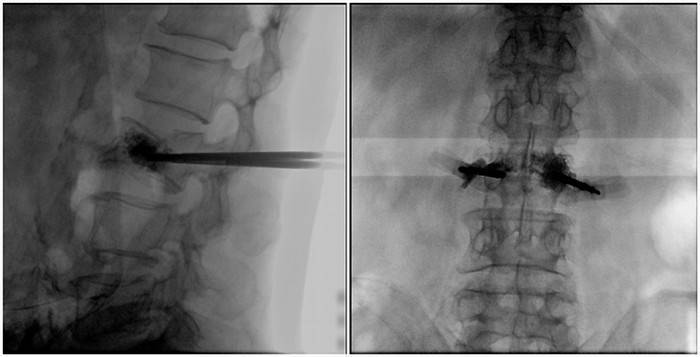

(2)術(shù)中切口5毫米,借助大視野平板C臂機(jī)PLX119C的高清圖像,確定進(jìn)針的方向及進(jìn)針的深度。經(jīng)椎弓根向椎體置管,建立通道,插入骨擴(kuò)張器(球囊)。球囊擴(kuò)張恢復(fù)椎體高度,并在椎體內(nèi)形成空腔,確定骨水泥的注入劑量,并注入骨水泥觀察其擴(kuò)散情況。

大平板C臂機(jī)的高清圖像

(3)注射過程需要C臂透視來查看骨水泥的分布情況,預(yù)防骨水泥外露進(jìn)入椎管內(nèi)引起神經(jīng)損傷。椎骨體內(nèi)骨水泥填充完好以后,拔出工作套筒按壓止血,并繼續(xù)俯臥位十分鐘,等待骨水泥硬化,最終手術(shù)圓滿完成。